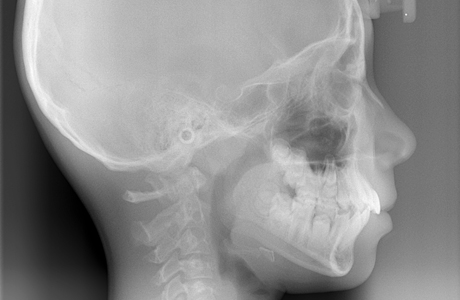

セファロレントゲンは頭部X線規格写真のことで、顔面や頭部を一定の規格に沿って撮影するレントゲンです。

同じ規格で撮影するので治療経過による顎や歯の位置の違いをくらべられます。矯正治療を行ううえでとても大切な情報です。「上下顎の大きさのバランスやずれの度合い」「歯と顎の位置関係」「歯の傾斜角」などの微細な情報を正確に把握ができます。撮影時間が短時間ですので、被曝線量も大幅に抑えられ、人体にも環境にも安心です。